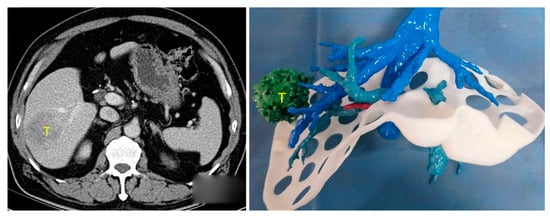

Traditionally, LCR surgical planning is based on a patient’s CT and/or MRI imaging. The surgeon uses 2D axial/multiplanar images and 3DVRs to determine appropriate resection planes and vascular/biliary reconstruction approaches. This requires using images on a 2D screen to construct a 3D mental visualisation of sophisticated patient liver structures. 3DPLMs can facilitate this task by providing a transparent [13,14,15,16,17,22,31], colour-coded [12,15,16,19,22,32,34,35,36,40], tactile [11,14,15,16,40], manipulable [11,14,16,19,29,31,40] and highly cognisable [14,15,16,17,19,29,31] representation of individualised patient liver anatomy, which improves comprehension of the complex and highly variable 3D spatial relationships between intrahepatic structures [14,16,19,22,29,31,33,40] and enhances cognitive localisation of liver tumours [15,16,17,29], as demonstrated in Figure 2. The improved anatomical perception assists surgeons in selecting the most appropriate surgical strategies [11,14,16,17,19,29,33,40], resection planes [13,16,17,33,40], and vascular reconstruction approaches [13,40].

HPB surgeons must be proficient in correlating mental reconstructions of patient liver anatomy with the actual surgical field during an operation [19]. This is particularly important during laparoscopic procedures where there is restricted anatomical overview [12,17]. Several articles argue, therefore, of the benefits of 3DPLMs for intraoperative guidance during LCR [9,13,19,22,33,40]. 3DPLMs can be oriented and compared directly to the surgical field, improving comprehension and navigation of the viewed anatomy (Figure 3) [9,19,33]. In this application, 3DPLMs can be used to better locate and identify lesions for resection [9,13,19], verify the position of vascular structures to inform potential adjustments to the resection plane [19,33], and better comprehend the locations of deeper anatomical structures hidden within the liver parenchyma [13,19,22]. 3DPLMs may also improve intraoperative detection of smaller metastases to ensure removal [13], and they may decrease the likelihood of intraoperative complications such as damage to intrahepatic vessels [19] and liver devascularisation [13,40].

Figure 2. Three-dimensional spatial location and relationship of liver tumour (T) with intrahepatic anatomy can be better appreciated using 3DPLM (right) compared to CT (left). Reprinted with permission under the open access from Cheng et al. [29].